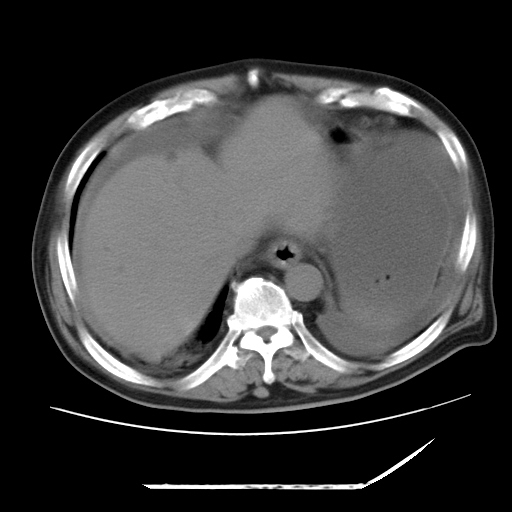

以下是引用zxl51642在2009-8-12 18:55:00的发言:[br]1、肠系膜脂肪浑浊,密度增高,腹水,支持腹膜炎诊断;2、右肾盂及输尿管中段结石,左输尿管起始段结石;3、胆囊切除术后改变?4、双侧胸膜腔少量积液;5、胰腺体积不大,勾勒清楚,肾前筋膜无增厚,不支持胰腺炎,请结合血尿淀粉酶及临床。